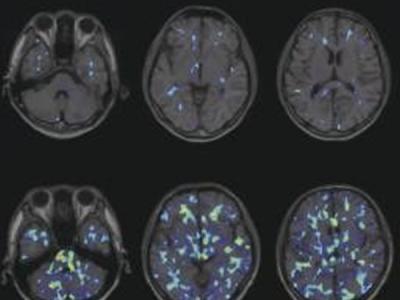

空气污染使50岁以上人群大脑变老三年

空气污染使50岁以上人群大脑变老三年 研究显示,城镇中较高水平的空气污染将使5...